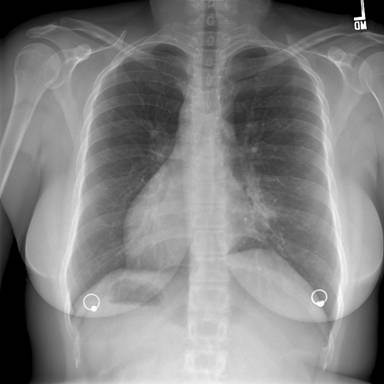

Figure 1: Posterior-Anterior Chest Radiograph—demonstrates dextrocardia and a gastric bubble under the right hemi-diaphragm consistent with situs inversus with a left sided infiltrate and tram tracking along the left heart border. Follow-up imaging with computed tomography (CT) of the chest, abdomen, and pelvis was obtained with selected images provided below: